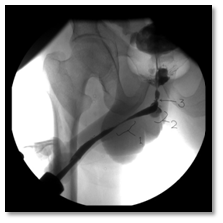

A 65 year old female referred from a peripheral hospital to the emergency comatosed, desaturated and intubated. Her relative gave history of long standing hypertension. On examination; patient was afebrile, intubated, Blood pressure was 160/100.Laboratory investigations were done and revealed a serum creatinine of 1990umol/l, BUN 74 mmol/l, serum K 6.3 mmol/l, Hb 8.2 gm, and WBCs 20110. Patient was admitted in ICU and diagnosed as uremic encephalopathy with pulmonary edema. Glasgow Comma Scale (GCS) was 8/15 and urethral catheter which was already placed drained 1000 ml/ 24 hours, turbid urine. Proper parenteral antibiotic was given according to culture and sensitivity test and patient underwent one session of hemodialysis(HD). Thereafter, serum creatinine dropped to 1002 mg/dl should be placed) BUN 54.3mmo/l and serum K 3.7 mmol/l. Non-contrast CT scan was performed combined with retrograde cystogram and showed mild bilateral backpressure, intra-abdominal free fluid collection and extravasation of contrast into the pelvis and abdominal cavity (Figure 3A & B).

Figure 3: Non-contrast CT Cystogram showing contracted bladder (A) and intraperitoneal fluid with extravasation of contrast into peritoneal cavity (A and B).